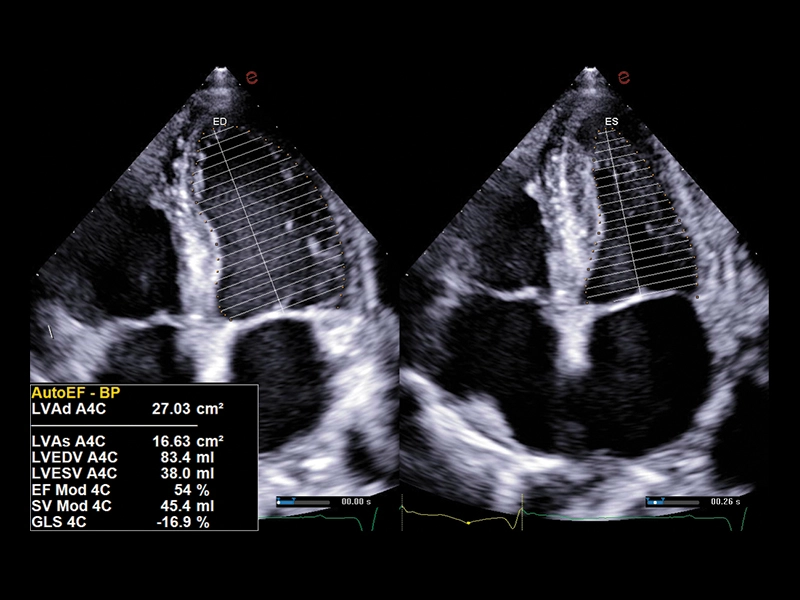

MyLab™X5 - XStrain

MyLab™X5 - XStrain

MyLab™X90 - XStrain™ LV Automatic assessment of global longitudinal strain in the left ventricle

MyLab™X90 - XStrain™ LV Automatic assessment of global longitudinal strain in the left ventricle

MyLab™Sigma - Left Ventricle XStrain 2D analysis

MyLab™Sigma - Left Ventricle XStrain 2D analysis